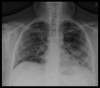

Coinfection with SARS-CoV-2 and Influenza A Virus in a 32-Year-Old Man

BACKGROUND There was a growing presumption that coinfection with severe acute respiratory syndrome coronavirus 2 (SARS-CoV-2) and another viral respiratory illness was nonexistent. Although there has been an increasing number of coinfection cases since the beginning of the SARS-CoV-2 pandemic, there is still a significant lack of information regarding the symptomatology, treatment, prognosis, and reasoning behind coinfection. This raises concern of the possibility of misdiagnosis or delay in treatment. CASE REPORT This case report discusses a coinfection of SARS-CoV-2 and Influenza A in a 32-year-old man to highlight that these viruses can coexist within the same patient. This patient unfortunately died of persistent respiratory failure after several days in the ICU. CONCLUSIONS Coinfection of SARS-CoV-2 and Influenza A can occur and lead to a poor prognosis.